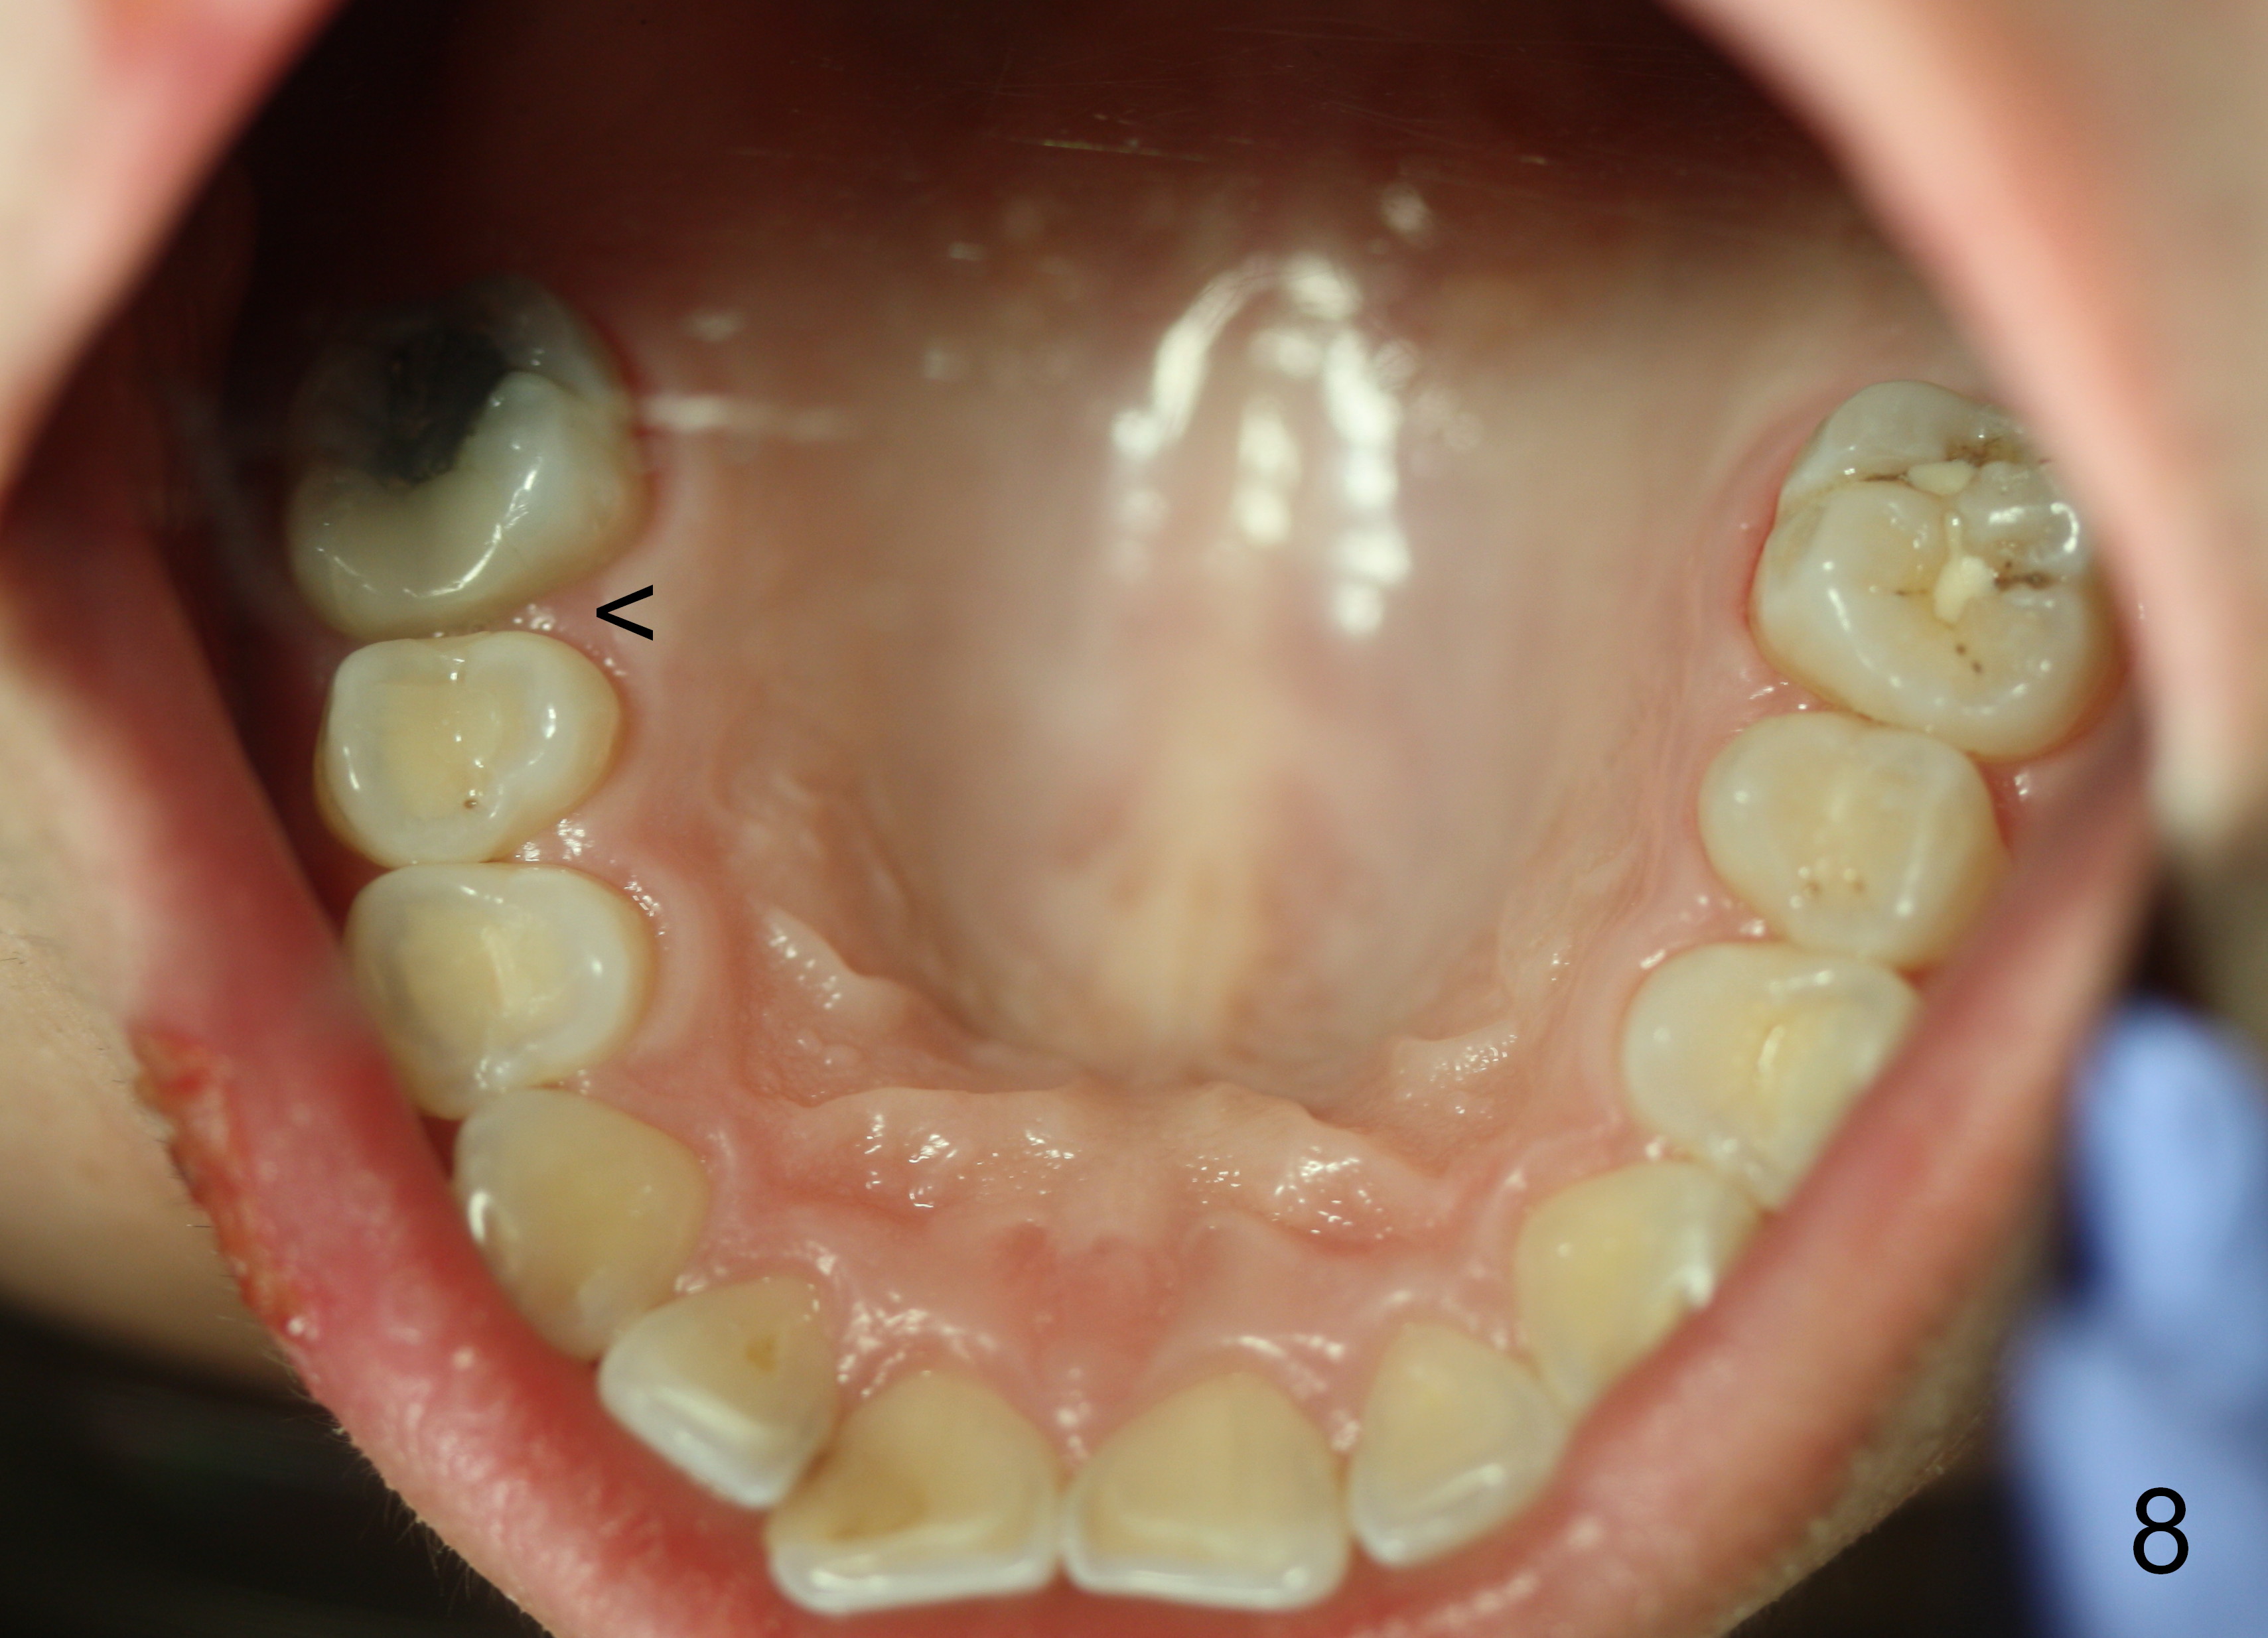

The panoramic X-ray (Fig.1) was taken on 12/12/2011 when the teeth #15 and 16 were extracted. The teeth #1 and 2 were removed half a year later. Bitewings (Fig.2-5), PAs (Fig.6,7) and upper occlusal mirror photo were taken on 02/11/2015. Pay attention to Fig.2.